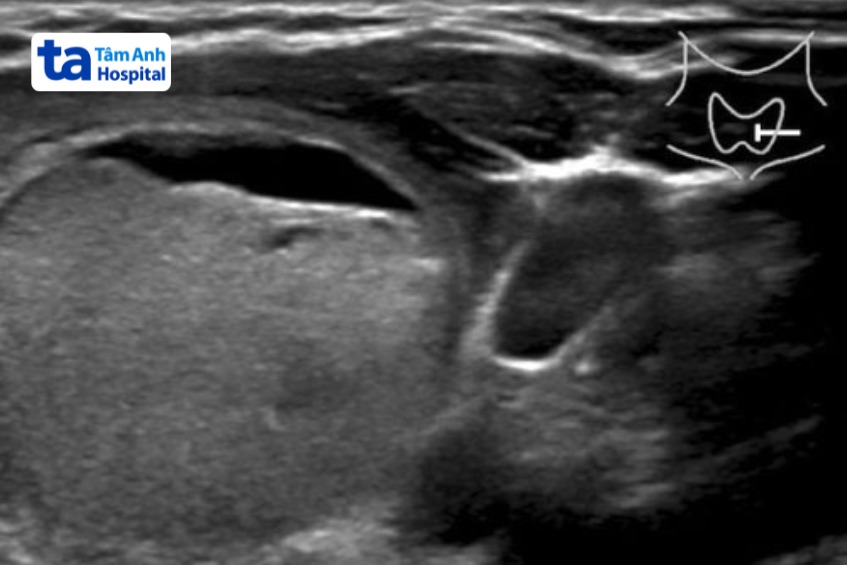

Hình ảnh nhân giáp được phân loại Tirads 3.